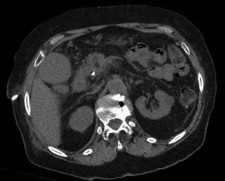

Figure 1.

Doctors at Zaragoza University Hospitals in Spain successfully utilized microwave energy to minimally invasively treat extrahepatic bile duct tumor obstruction.

The doctors at Zaragoza University Hospital in Spain applied microwave energy to destroy tumor growth within the main bile duct to reestablish and maintain normal bile flow. A flexible catheter with a microwave antenna tip is inserted into the liver under fluoroscopy into the bile duct with blockages. Once the antenna is positioned in the blockage, microwave energy is applied using preset power, temperature and time durations endocavitary. The antenna is pulled along within the duct with the blockage, and the energy application is repeated until the desired length of the duct is treated. The doctors removed the microwave catheter and verify bile-duct flow with fluoroscopy.  Doctors place resorbable prosthesis, dilation stent balloon, and 5F catheter for 24hrs. No complications were observed. The microwave energy application is controlled with direct temperature feedback from the ablation antenna during the procedure to ensure safety and efficacy.

AveCure® microwave ablation system is successfully treating tumors in bile-duct using a minimally invasive technique, the percutaneous transhepatic cholangiography (PTC) incision through the skin to access the tumor through liver, and patient is left with a small hole in the skin which quickly heals with almost no scar after the procedure.  AveCure® system utilizes a smart antenna in either probe or catheter format and microwave energy controller to select the correct size, temperature, and timer settings appropriate for safe, effective and predictable treatment.